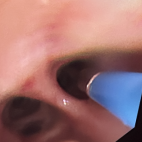

第一步:在超導(dǎo)可視系統(tǒng)的指導(dǎo)下,利用可彎曲自如的超軟導(dǎo)管,由口腔、氣管氣道、肺部,通過壓強差的原理方式,將氣管氣道膿性分泌物或痰液痰栓吸出,疏通氣道。

第二步:直接靶向給藥介入,消除肺部氣管氣道炎癥,修復(fù)受損氣道黏膜及肺泡的呼吸膜受損的位置。